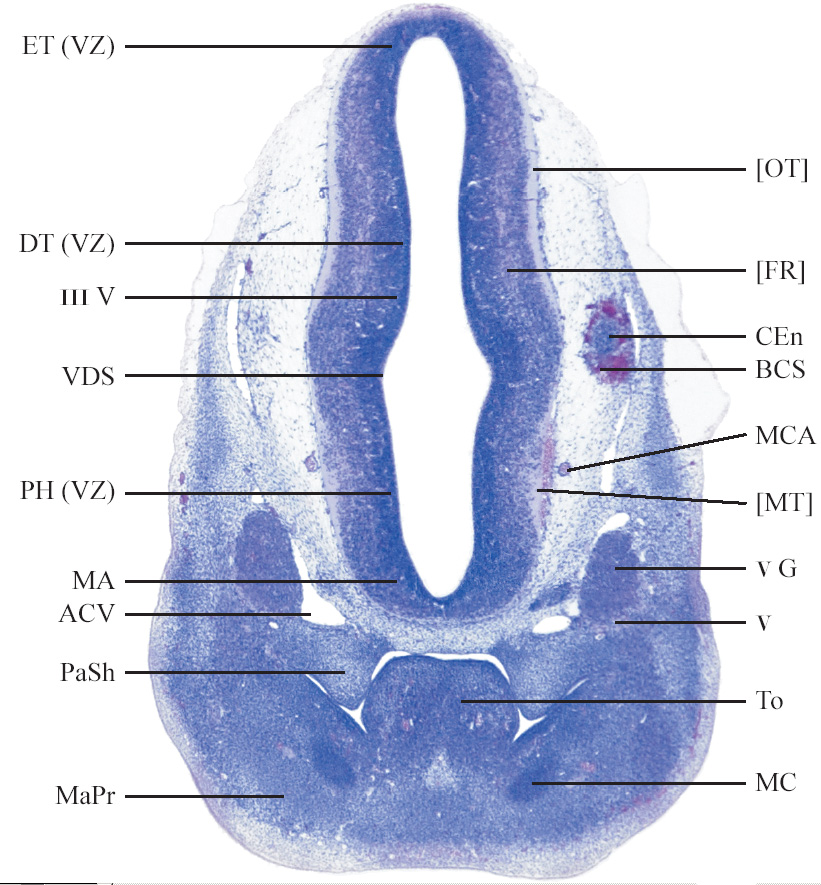

C57BL/6J GD12 Mouse Brain Atlas

Slides from U. Schambra, coronal cuts with slides at every 5th section, with a hematoxylin and eosin (H & E) stain

Currently on section 115.